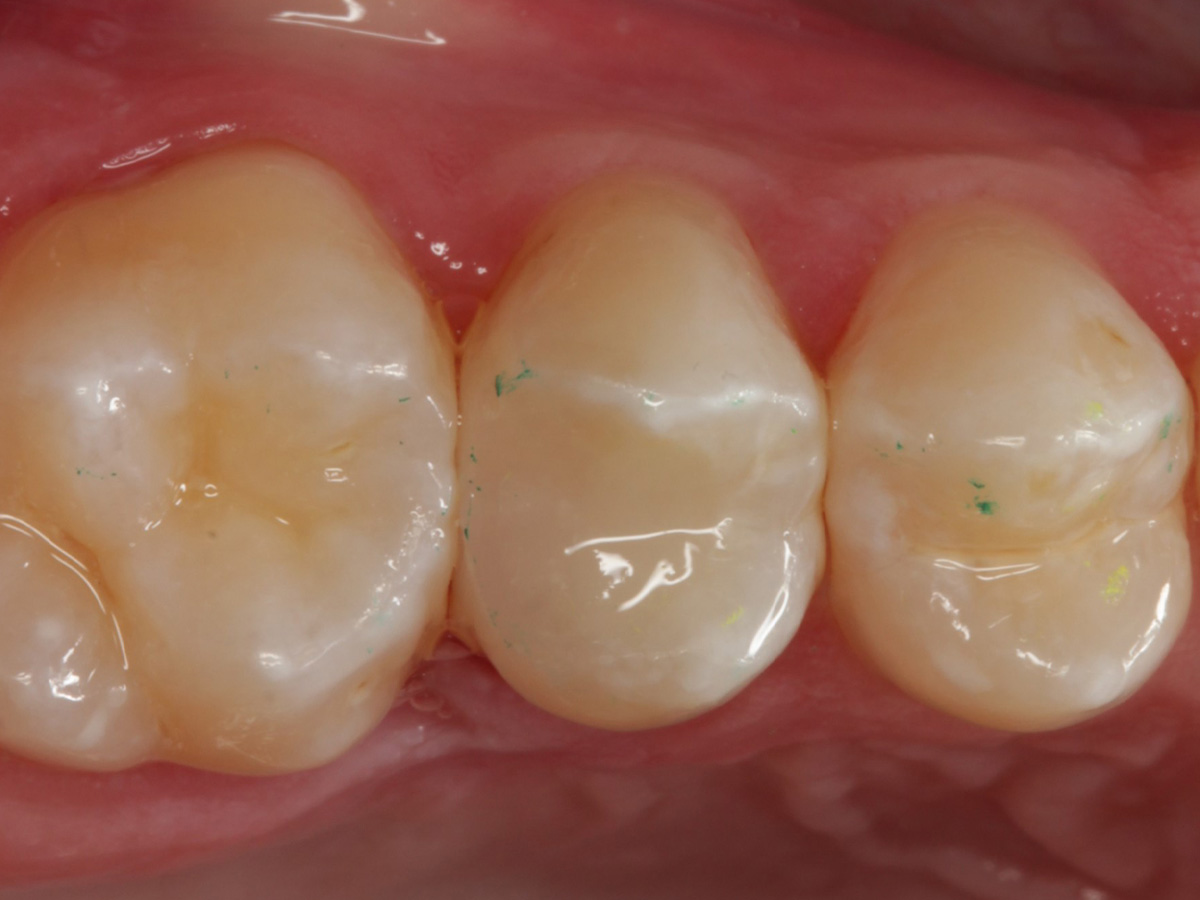

Abbildung 28

Kompositrestauration nach „Schachtverschluß“; keine Krone geplant

Abbildung 29

Fazit

Also ich kann jetzt für mich sagen, dass die neuen Evolve Matritzen nochmal ein richtiger Schritt nach vorn hinsichtlich Formstabilität, Kantensteifigkeit, und aber insbesondere der Behandlung extrem tiefreichender (approximaler) Defekte sind. Obwohl diese Matrizen angeblich so dick sind wie die Biofit-Matrizen, sind sie gefühlt dünner und dabei gleichzeitig stabiler. Ein Riesenvorteil bei tiefer Zerstörung ist diese zusätzliche "Lasche", mit der fast alle Defekte sauber eingefasst werden können.